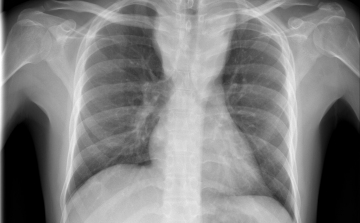

Magyarországon halnak meg a legtöbben tüdőrákban az EU-ban

Az Európai Unióban Magyarországon a legmagasabb, az összes halálok között 27 százaléknyi a tüdőrák okozta halálozások aránya - hangzott el az M1 aktuális csatorna csütörtöki műsorában.